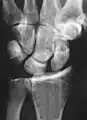

- Scapholunate ligament disruption associated with a Colles' fracture